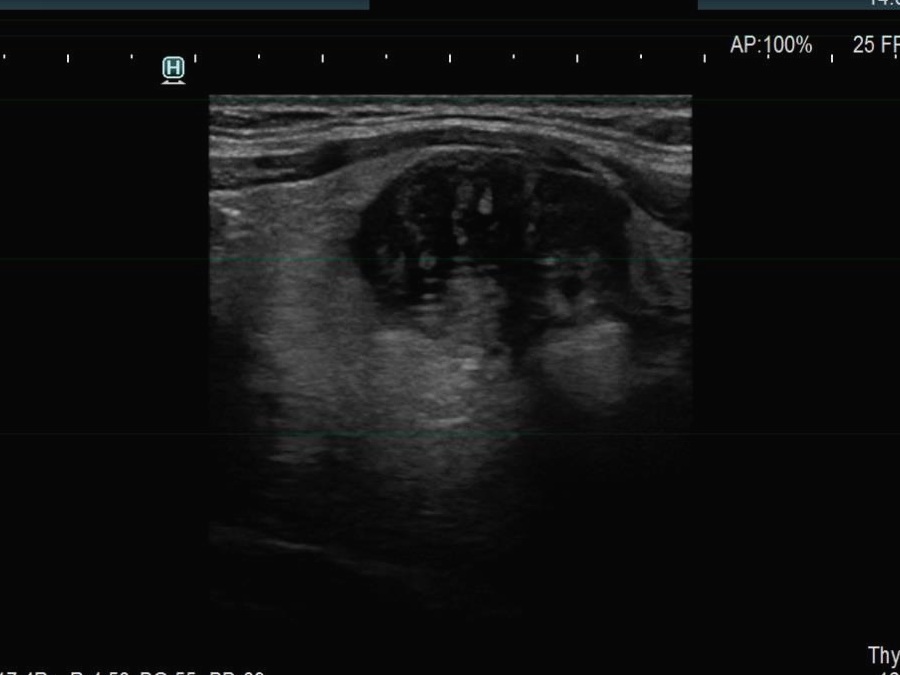

Ultrasonography. The thyroid was echonormal. There were multiple smaller lesions in the right lobe. The largest one was minimally hypoechoic and presented with halo and perinodular vascularity. A large, hypoechoic nodule occupied almost the entire left lobe. The nodule had lobulated and spiculated margins and bulged into the sternocleidomastoid muscle. The vascularity was not specific.

This case illustrates the weakness of ultrasound in judging extrathyroidal extension.

It is mandatory to check the settings before every examination regarding the echogenicity of the strap muscle. If we do not see echoes within the darkest parts of the muscle, we should either increase the gain or decrease the frequency.